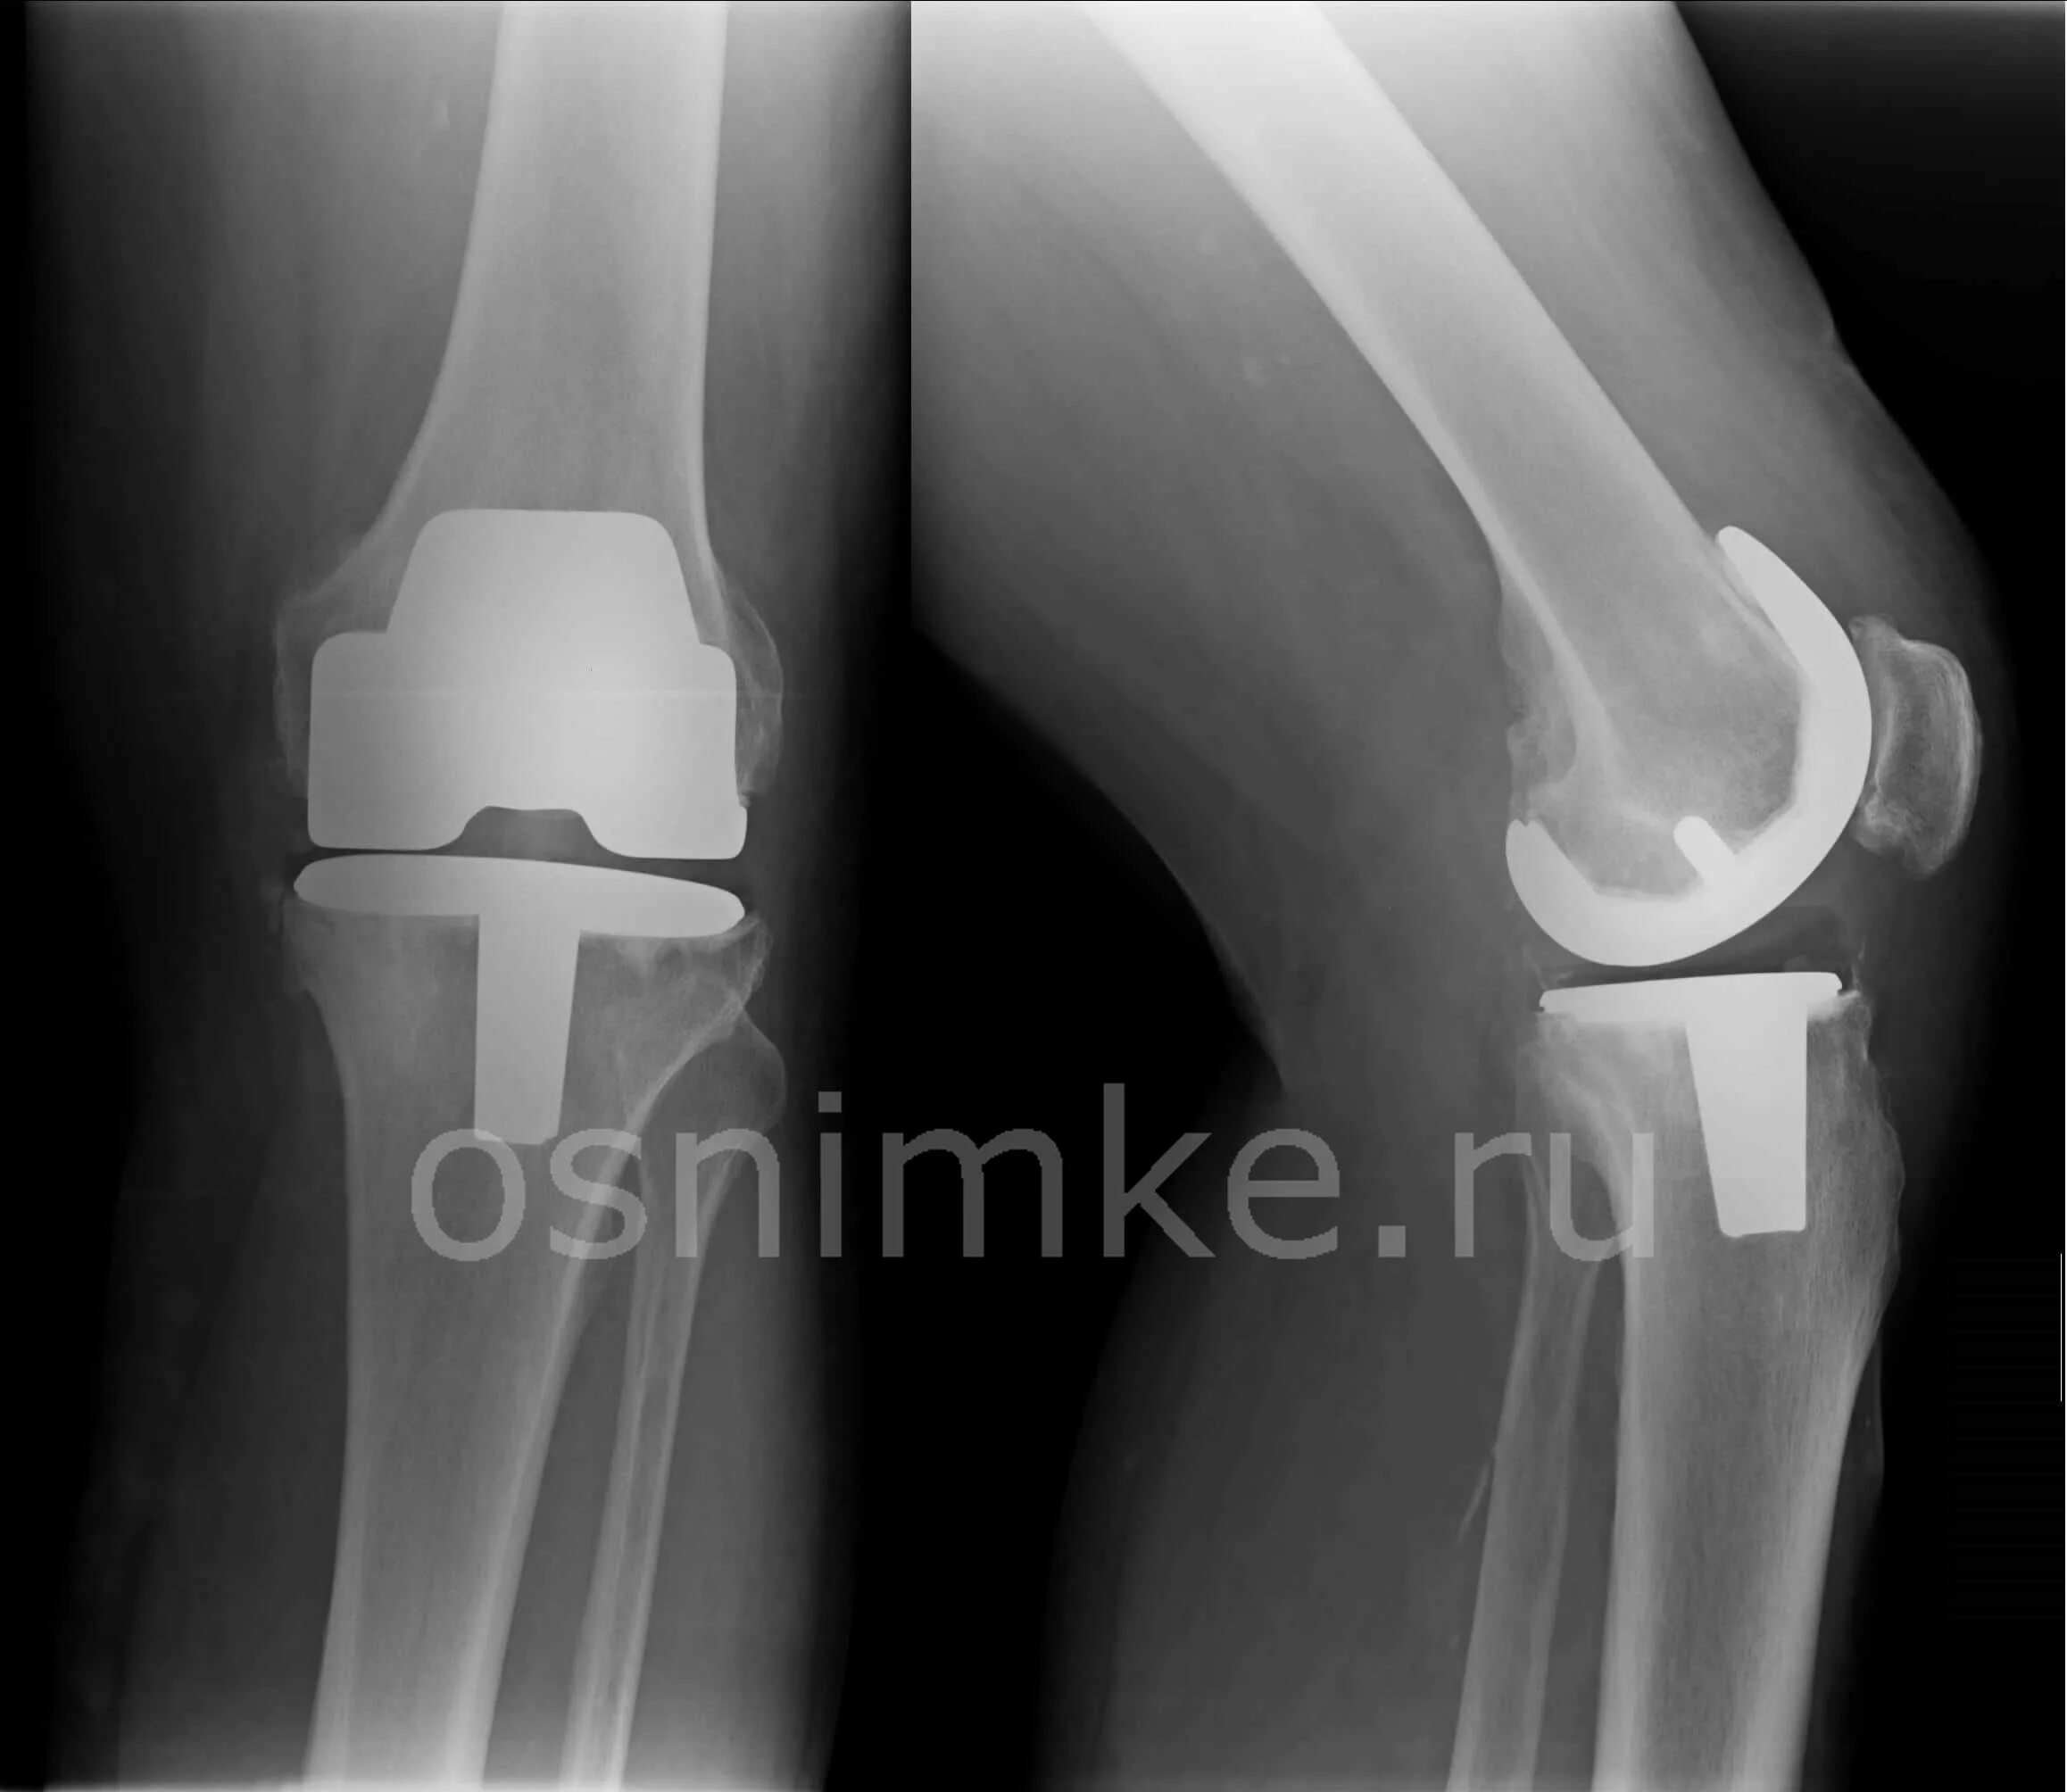

Рентгенография коленного сустава 2 проекции